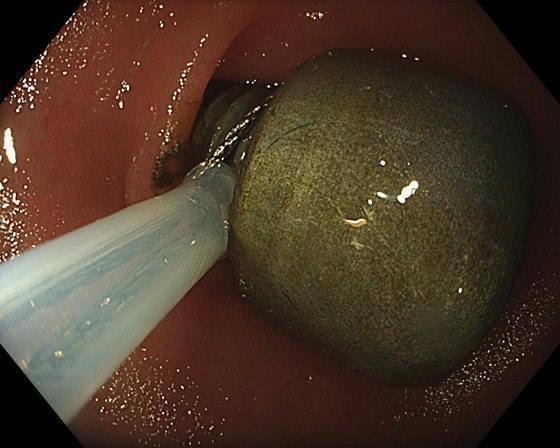

Эндоскописты Детского научноклинического центра им. Л. М. Рошаля помогли годовалому мальчику, который случайно проглотил металлический болт.

Рентген показал крупное инородное тело в желудке. Врачи провели малотравматичную эндоскопическую операцию — без разрезов, с помощью специальной петли. Процедура заняла около 15–20 минут.